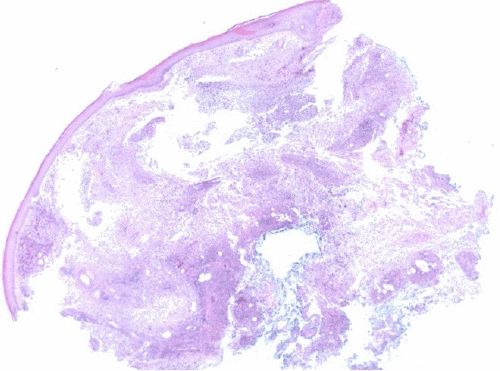

Upper endoscopy with endoscopic ultrasound was performed to evaluate for malignancy—no pancreatic mass was identified. Given the draining nodules on physical exam were suggestive of fat necrosis and an extensive rheumatologic workup of the patient's polyarthritis was negative, a skin biopsy of the left wrist nodule was performed. This demonstrated dense dermal and subcutaneous necrotizing neutrophilic inflammation consistent with pancreatic panniculitis (Figure 5).1 Wound culture from the nodules was negative for pathogenic organisms.

Figure 5. Representative Histopathological Images at (A) 20x, (B) 100x, and (C) 200x Magnification of Left Wrist Punch Biopsy. Published with Permission

A.

B.

C.

Images demonstrate diffuse dermal and subcutaneous necrotizing neutrophilic inflammation.